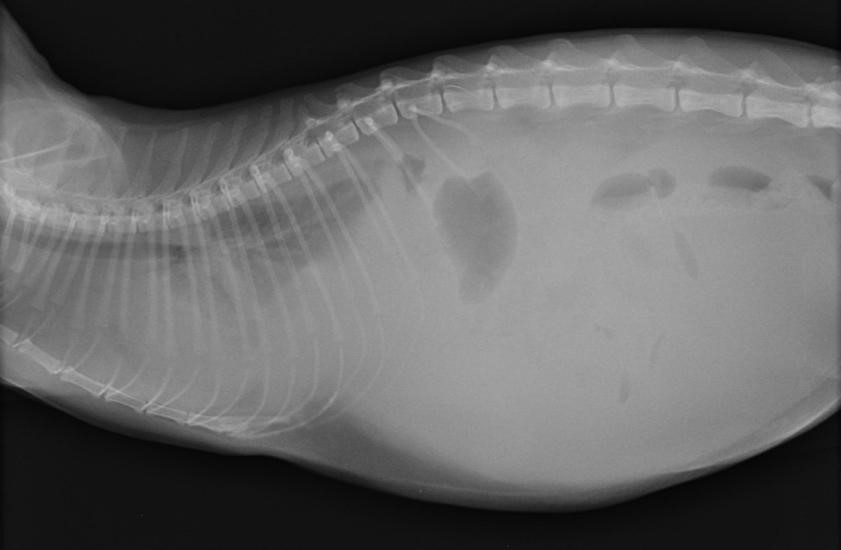

По анализу мочи судят о фильтрационной способности почек, особое внимание обращают на количество белка в моче (оно повышается). Для визуализации жидкости в брюшной полости используют такие методы диагностики, как рентгенография и ультразвуковое исследование

Для визуализации жидкости в брюшной полости используют такие методы диагностики, как рентгенография и ультразвуковое исследование.

На рентгенологическом снимке при небольшом количестве асцитной жидкости оценивают размеры печени, почек, лёгких, сердца, обращают внимание на наличие или отсутствие новообразований. Если же количество жидкости велико, то рисунок органов брюшной полости становится нечётким